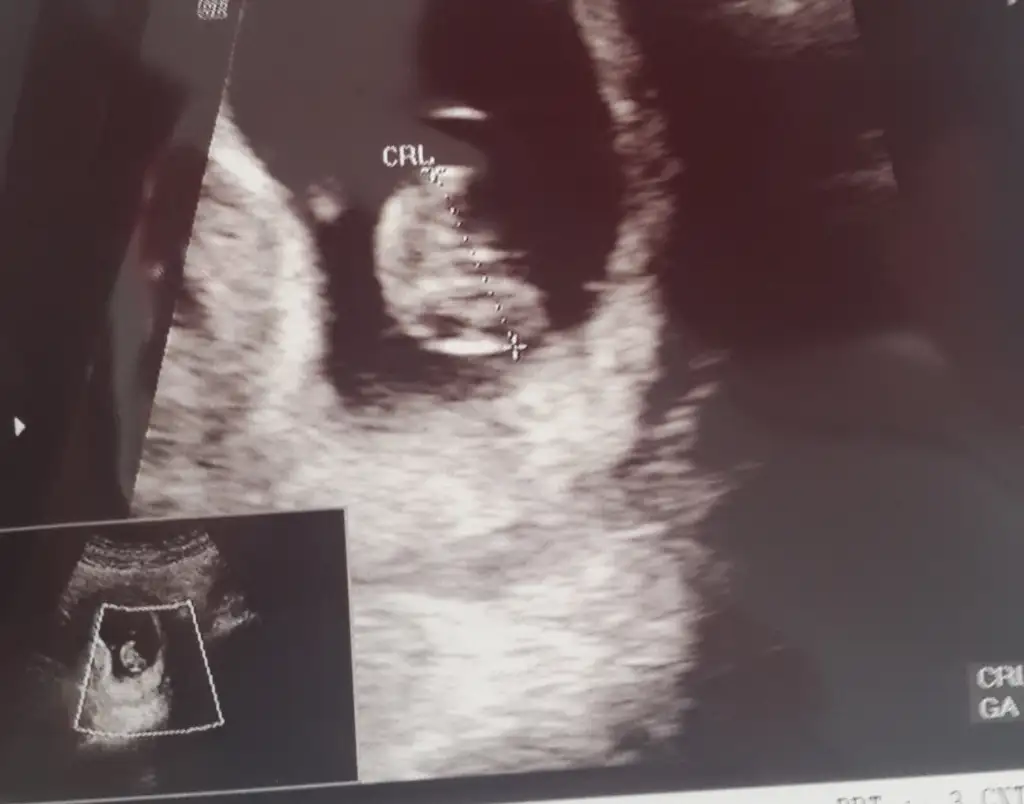

Ben anlamadim. Benimki Erkek mi kiz mi 13haftalikken erkek demişti doktor 15 haftalikken %90 kiz dedi yardımcı olur musunuz 7haftalik goruntusu

herkese merhaba bugün doktor kontrolünden aldığım ultrason görüntüsüyle geldim buraya,8 haftalık olduğunu söyledi doktorum. ben de merak ediyorum açıkçası sizce tahminleriniz nelerdir kız mı erkek mi? benim içime kız doğuyor sürekli kız bebek rüyaları görüyorum :)